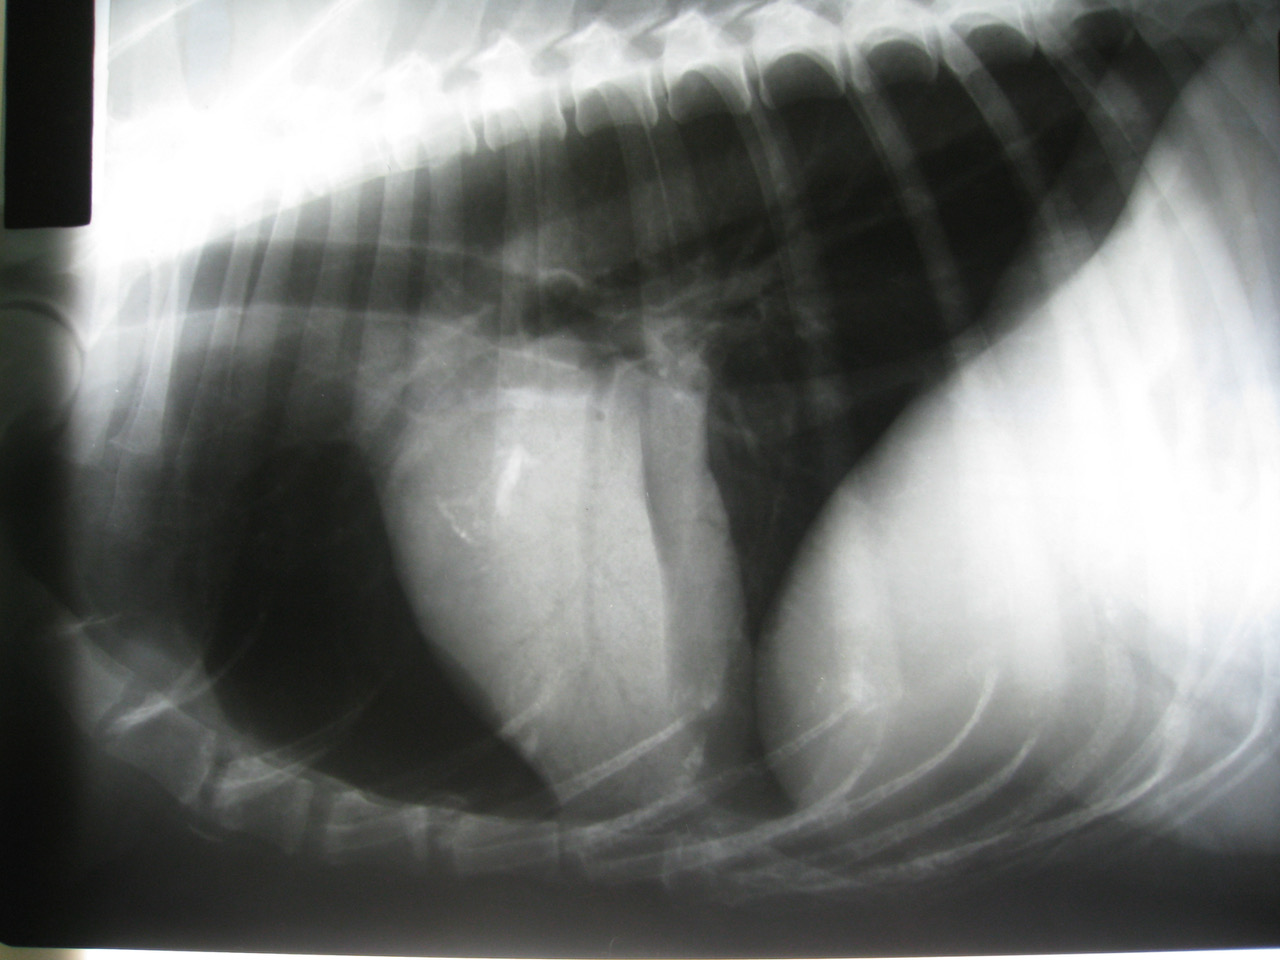

🖼️ My favourite image *(MRI, CT, US, Rads)*

Although this image is not very good quality, I love this image for the distracting heart mineralization and the way the consolidated lung overlays the heart perfectly. This image is a lesson in seeing the absence of something, rather than the presence. If you flip the image vertically, (in the old days, put in on the viewer the other way up) it demonstrates why it is called a bronchial tree.